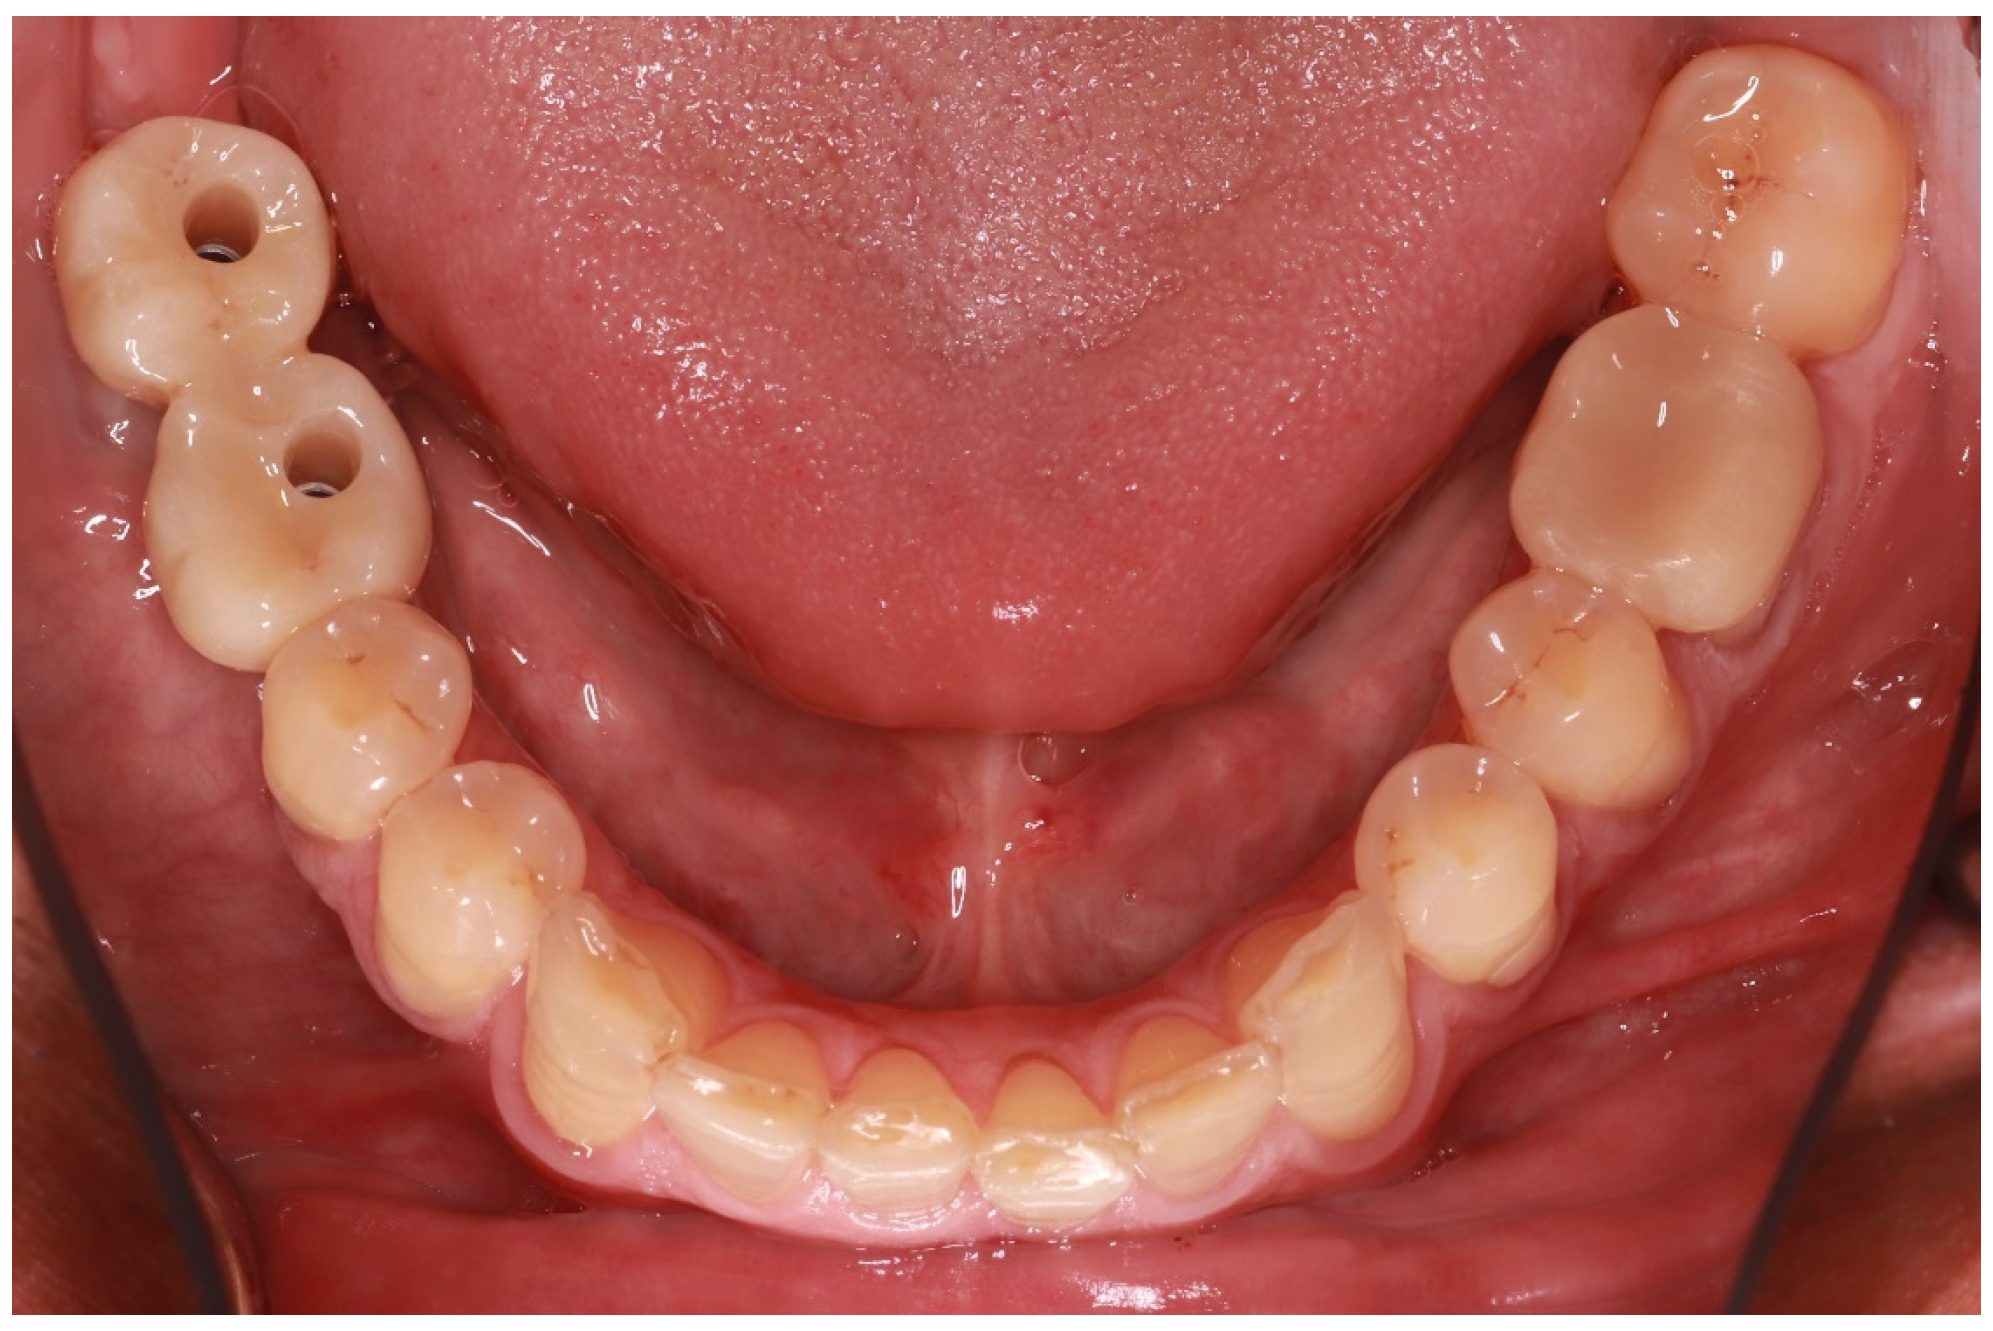

Five years later, the patient returned for the rehabilitation of missing teeth No. #46 and 47. Tooth No. #48 was extracted and two implants were placed. After 4 months, two screw-retained implant-supported crowns were delivered. The endocrown on tooth No. #36 was still in place and in excellent condition (Figure 9).

The Modified US Public Health Service (USPHS) criteria were used for the objective evaluation of the restoration at the five-year recall [19]. Two authors (E.P. and T.K.S.), other than the one who delivered the endocrown (D.P.), were chosen to evaluate the restoration, and both of them rated the restoration as “Alfa” in all of the included parameters, which corresponds to the ideal clinical situation. Radiographic evaluation (Figure 10) did not reveal any pathology or defective areas.

Figure 9. Occlusal view five years after the endocrown delivery on tooth No. #36. The restoration is still in place, scoring “Alfa” in all of the USPHS criteria utilized for the re-evaluation.